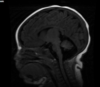

Q

A

Esclerose mesial temporal

Observe a perda de volume, que indica atrofia e causa aumento secundário do corno temporal do ventrículo lateral.

O sinal alto no hipocampo reflete a gliose.

How well did you know this?

Qual o padrão da Esclerose mesial temporal?

Atrofia hipocampal e hipersinal T2. Cerca de 10% dos casos são bilaterais (dificulta o diagnóstico). A etiologia é desconhecida, mas há uma relação entre STM e convulsões febris prolongadas no início da vida A esclerose mesial temporal pode ocorrer em associação com outras patologias, principalmente displasia cortical focal (dual pathology).